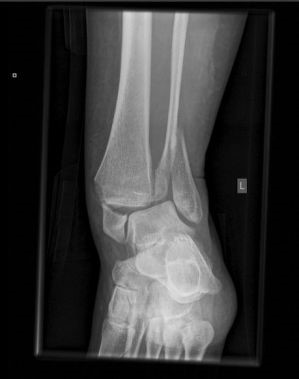

Een enkel kan op meerdere plaatsen breken. De enkel kan zowel aan de buitenkant (onderste deel van het kuitbeen) als aan de binnenkant breken (deel van het scheenbeen) en in enkele gevallen ook aan de achterkant (deel van het scheenbeen). Ook kunnen deze plaatsen gecombineerd voorkomen, al dan niet in combinatie met een letsel van de enkelbanden. Het meest voorkomend is de breuk aan de buitenkant (van het kuitbeen), dat vaak ontstaat ten gevolge van een ernstige verzwikking, verstappen of een val.

Voor het aantonen van de breuk dient er een Röntgenfoto te worden gemaakt. Hierop kan ook worden gezien op welke plaats(en) het bot gebroken is.